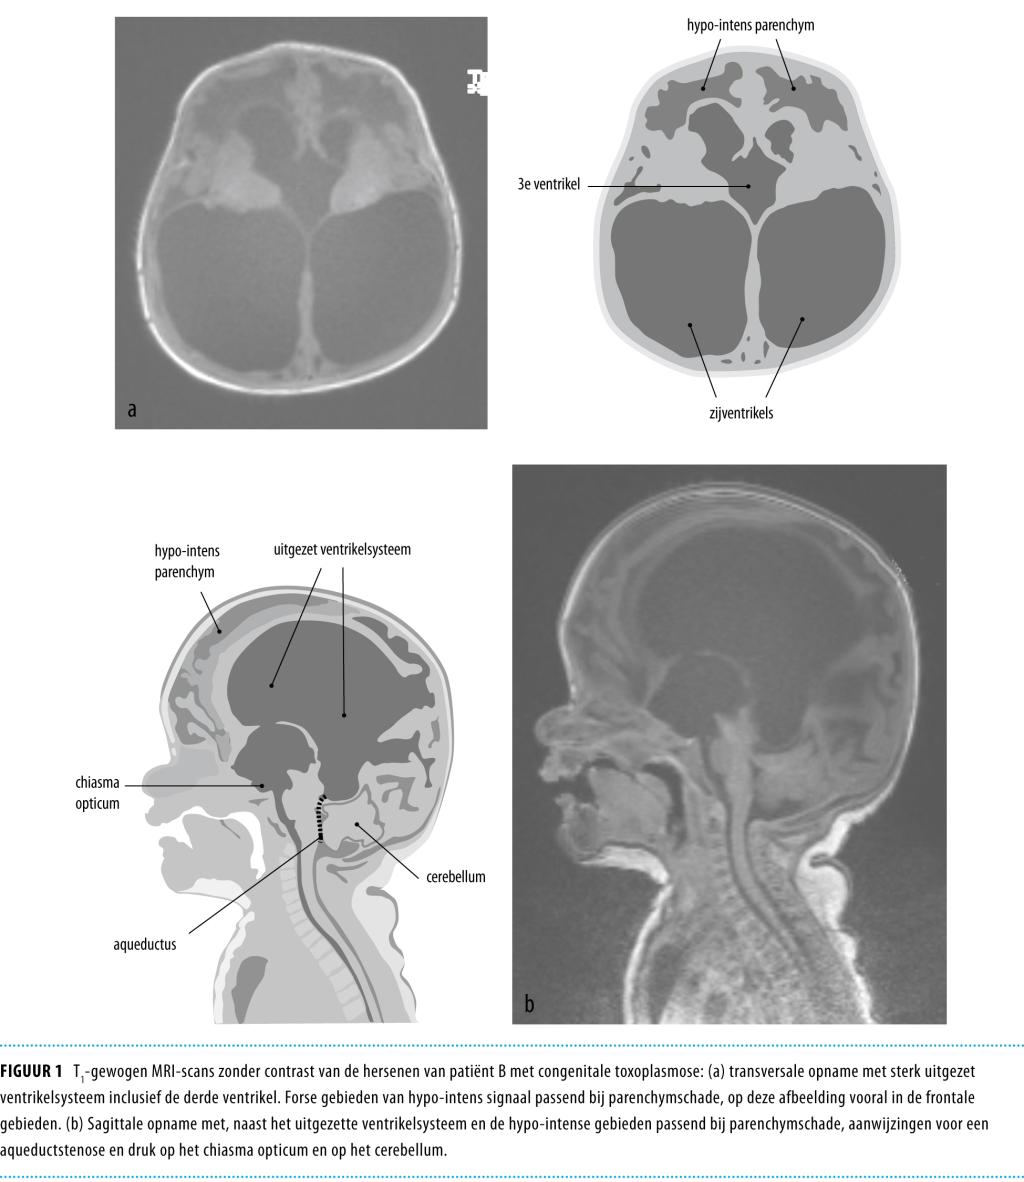

Bij echo-encefalografie werden fors verwijde ventrikelruimten gezien. Aanvullend onderzoek toonde anemie en trombopenie met in de liquor verhoogde aantallen leukocyten (29 cellen/μl; referentiewaarde: 0-5), een toegenomen concentratie lactaat (4792 μmol/l; referentiewaarde: 900-2800) en totaal eiwit (6650 mg/l; referentiewaarde: 150-400) bij een verlaagde glucosewaarde (1,1 mmol/l; referentiewaarde: circa 0,7 maal de bloedwaarde). MRI van het cerebrum toonde een hogedruk-hydrocefalus met ernstige aqueductstenose, uitgebreide encefalomalacie en compressie van cerebellum en chiasma opticum (figuur 1). Funduscopie toonde beiderzijds uveïtis posterior met meerdere subretinale afwijkingen. Serologische uitslagen waren positief voor T. gondii (IgG: 1163 IU/ml; IgM: positief; uitgevoerd door het UMC St Radboud).

Figuur 1